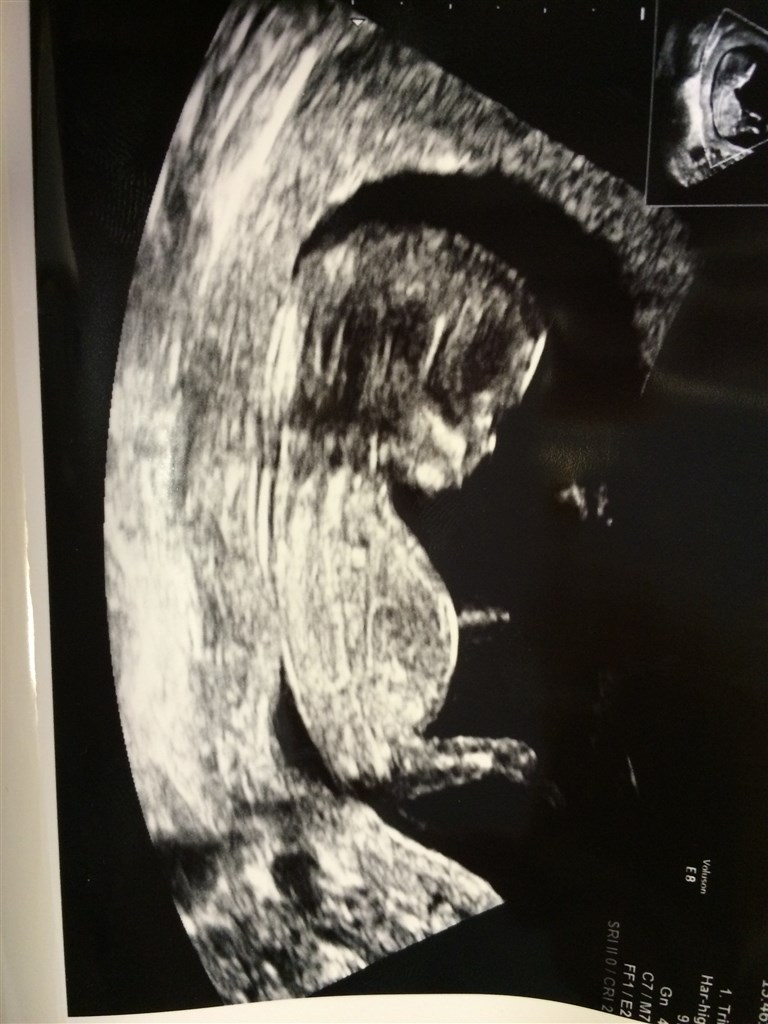

Har idag været til Nakkefoldscanning! Der lå den fineste lille bebs og var noget så livlig!

Så idag fik jeg da smil på læben igen da jeg så min lille bebs ligge og lege inde i maven